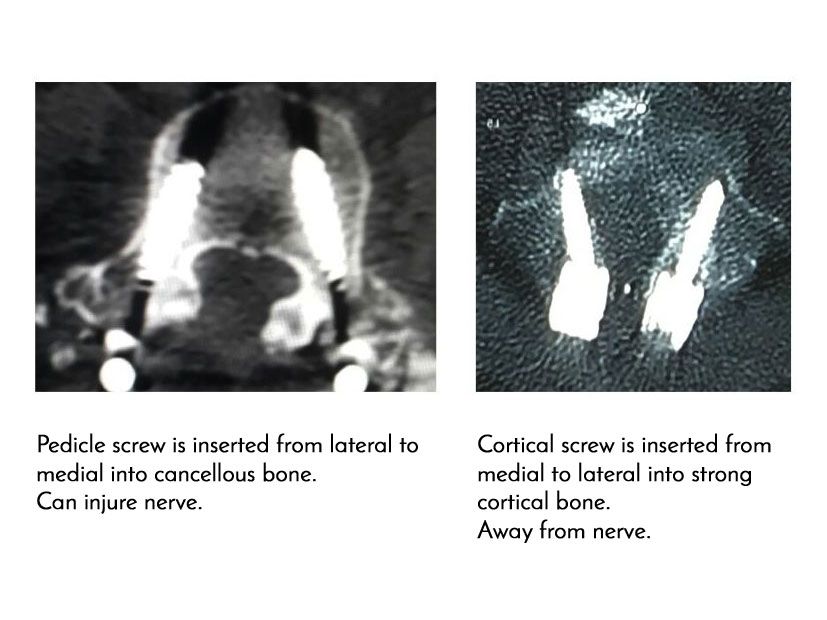

New technique for inserting screws in osteoporotic patients